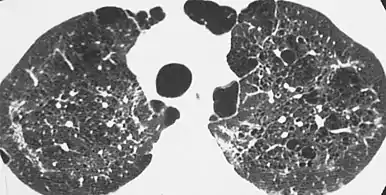

X-ray and CT of ground glass opacities and pneumothorax in pneumocystis pneumonia.[7]

The diagnosis can be confirmed by the characteristic appearance of the chest X-ray and an arterial oxygen level (PaO2) that is strikingly lower than would be expected from symptoms. Gallium 67 scans are also useful in the diagnosis. They are abnormal in about 90% of cases and are often positive before the chest X-ray becomes abnormal. Chest X-ray typically shows widespread pulmonary infiltrates. CT scan may show pulmonary cysts (not to be confused with the cyst-forms of the pathogen).